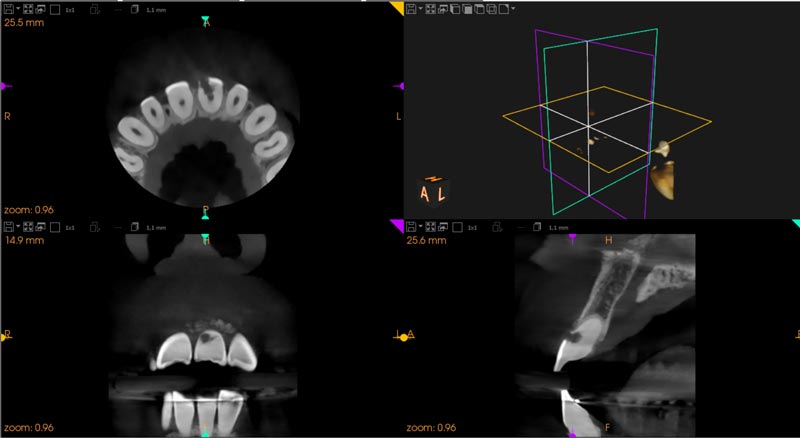

CBCT

En determinados casos, para realizar un diagnóstico preciso y planificar adecuadamente el tratamiento endodóntico, es necesario complementar el estudio radiográfico convencional con una tomografía computarizada de haz cónico (CBCT).

El CBCT proporciona una imagen del diente en tres dimensiones, lo que resulta útil cuando la anatomía es compleja o cuando existen dudas que no se pueden resolver con una radiografía convencional. Nos permite evaluar la presencia de conductos adicionales, calcificaciones, reabsorciones radiculares o lesiones óseas guiándonos a un diagnóstico y tratamiento adecuado.

Esta prueba se solicita únicamente cuando está clínicamente indicada, y resulta especialmente útil en casos complejos, retratamientos endodónticos o cuando existe sintomatología persistente sin una causa clara en las radiografías convencionales.

Aunque en Endodoncia Denia no disponemos de CBCT propio, colaboramos con centros radiológicos y clínicas de confianza, donde el estudio se realiza siguiendo protocolos actuales y con la mínima dosis de radiación necesaria.

El objetivo de solicitar un CBCT es conocer mejor el caso antes de tratar, aumentando las posibilidades de éxito y la conservación del diente a largo plazo.

El uso del CBCT permite valorar con mayor precisión la extensión de la reabsorción y definir mejor el abordaje terapéutico.

Imágenes:

Imagen de CBCT mostrando el alcance de una Reabsorción Cervical Invasiva.

Caso resuelto mediante endodoncia y tratamiento quirúrgico.

En estos casos, el CBCT resulta una herramienta especialmente útil, ya que permite estudiar la perforación en tres dimensiones y planificar el tratamiento de forma precisa y segura.

Corte Axial de CBCT donde observamos material de relleno fuera del espacio del conducto radicular en el diente 2.2

Radiografías periapicales inicial y final con la resolución del caso

Imágenes: Imagen de CBCT que muestra una fractura ósea de un paciente tras haber sufrido un trauma dental.

Antes de llevar a cabo la intervención, es imprescindible realizar una valoración mediante CBCT para estudiar la anatomía y planificar el tratamiento con precisión.